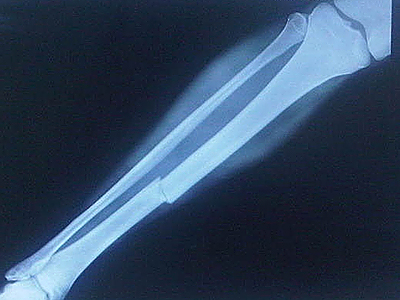

“While I was there, they had an Olympic qualifier event at the training center for taekwondo,” Allen said. “I thought, ‘Wow. There’s a sport that needs a doctor.’ There’s a very high probability of concussions; head shots get you the highest scores. They also break a lot of bones and they blow out their knees.”

Allen’s training as an orthopaedic surgeon comes in handy. At every national competition, she treats a laundry list of injuries: fractures, concussions, dislocations.